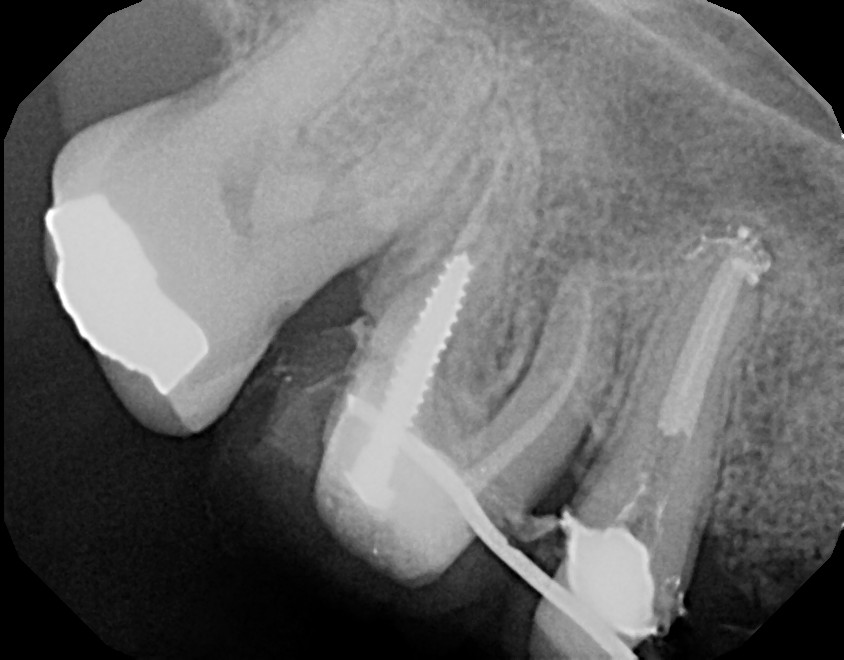

This is a root canal retreatment procedure of 2nd maxillary premolar (tooth #4) due to a missed canal which caused infection. An additional canal was located, both canals were retreated and the tooth will be restored with a crown. The first maxillary molar (tooth #3) needs to be retreated (redone) as well because of infection, due to inadequate root canal therapy. Always ask your general dentist for a referral to an endodontist (root canal specialist) for your root issues.